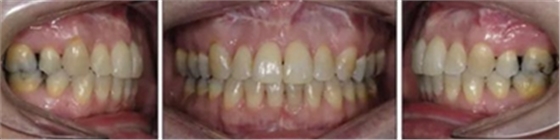

患者側(cè)貌改善,下唇唇肌緊張消失,上下唇可自然閉合。磨牙及尖牙關(guān)系糾正至I類(lèi),覆合覆蓋正常。上下頜弓型糾正至卵圓形,牙弓寬度增加。頭影測(cè)量分析示SNA角81.8°,ANB角3°。頭影測(cè)量重疊圖示下頜骨向后旋轉(zhuǎn),垂直面高度略有增加。

19個(gè)月后復(fù)查,情況穩(wěn)定,牙弓寬度穩(wěn)定。